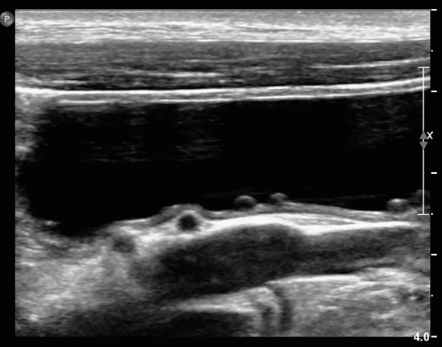

간혹 개나 고양이 환자들의 방광염 검진을 하다보면 방광벽에 동그란 물주머니들이 보이는 경우가 드물지만 있는데

이번 환자처럼 여러개가 있다면 끔찍할만큼 혐오스럽게 생겼기에 놀래고

방광의 등쪽에 위치하고 있어 방광염보다는 오히려 종양성 신생물의 가능성을 고려하는게 병리학적 접근일 수 있다.

하지만 방광에서 주로 발생하는 이행상피암종의 일반적 양상에 비해 너무 구획이 잘 일어나 있어서 종양으로 확신하고 말하기 어려운 소견이기도 하다.

이번 증례는 그런 현상을 보이는 개에서의 진단 결과를 종합한것으로 특히 대장균 기원의 방광염 환자에 대한 자료이다.